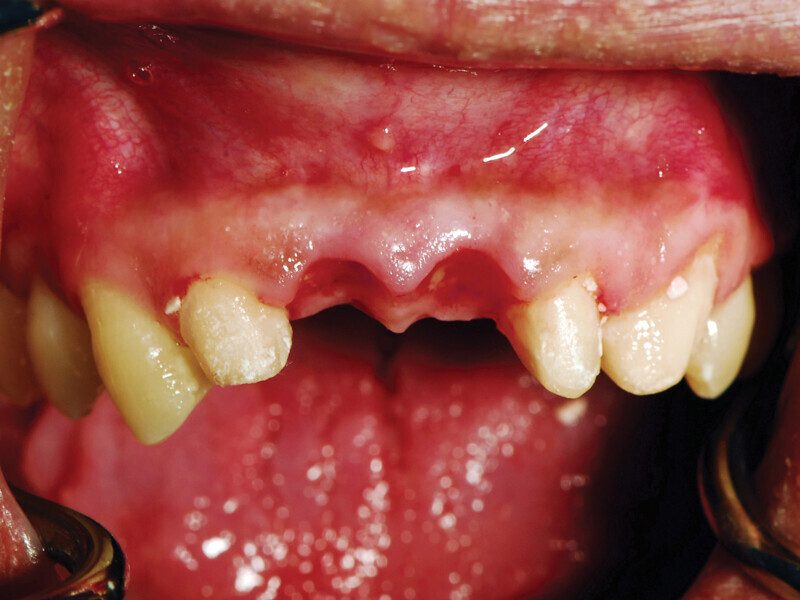

Fig. 6: Buccal view of the anterior maxilla demonstrating preservation of the papilla due to the provisional bridge. (Photo provided by Dr. Gregori M. Kurtzman)